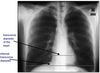

How is heart size assessed on CXR?

A

maximum transverse diameter of the heart must be less than 50% of the maximum transverse internal diameter of the thoracic cavity

(must be erect, PA, full inspiration)

only in adults; does not work if hyperinflated (e.g. smokers, COPD, airway obstruction)